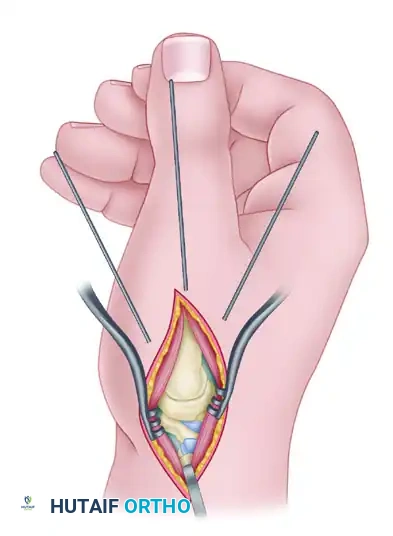

Option B: Kirschner Wire Fixation

If K-wire fixation is chosen (often preferred in cases of small trapezial bone stock where a plate might cause comminution), drive three 1.1-mm or 1.6-mm wires retrograde from the metacarpal into the trapezium.

The first pin follows the planned longitudinal axis of the bone fusion. The other two pins should diverge 10 to 20 degrees from this central axis to provide rotational stability.

Take care to avoid pin penetration into the scaphotrapeziotrapezoid (STT) joint. Leave the pins protruding slightly outside the skin, capped, for later removal in the clinic.